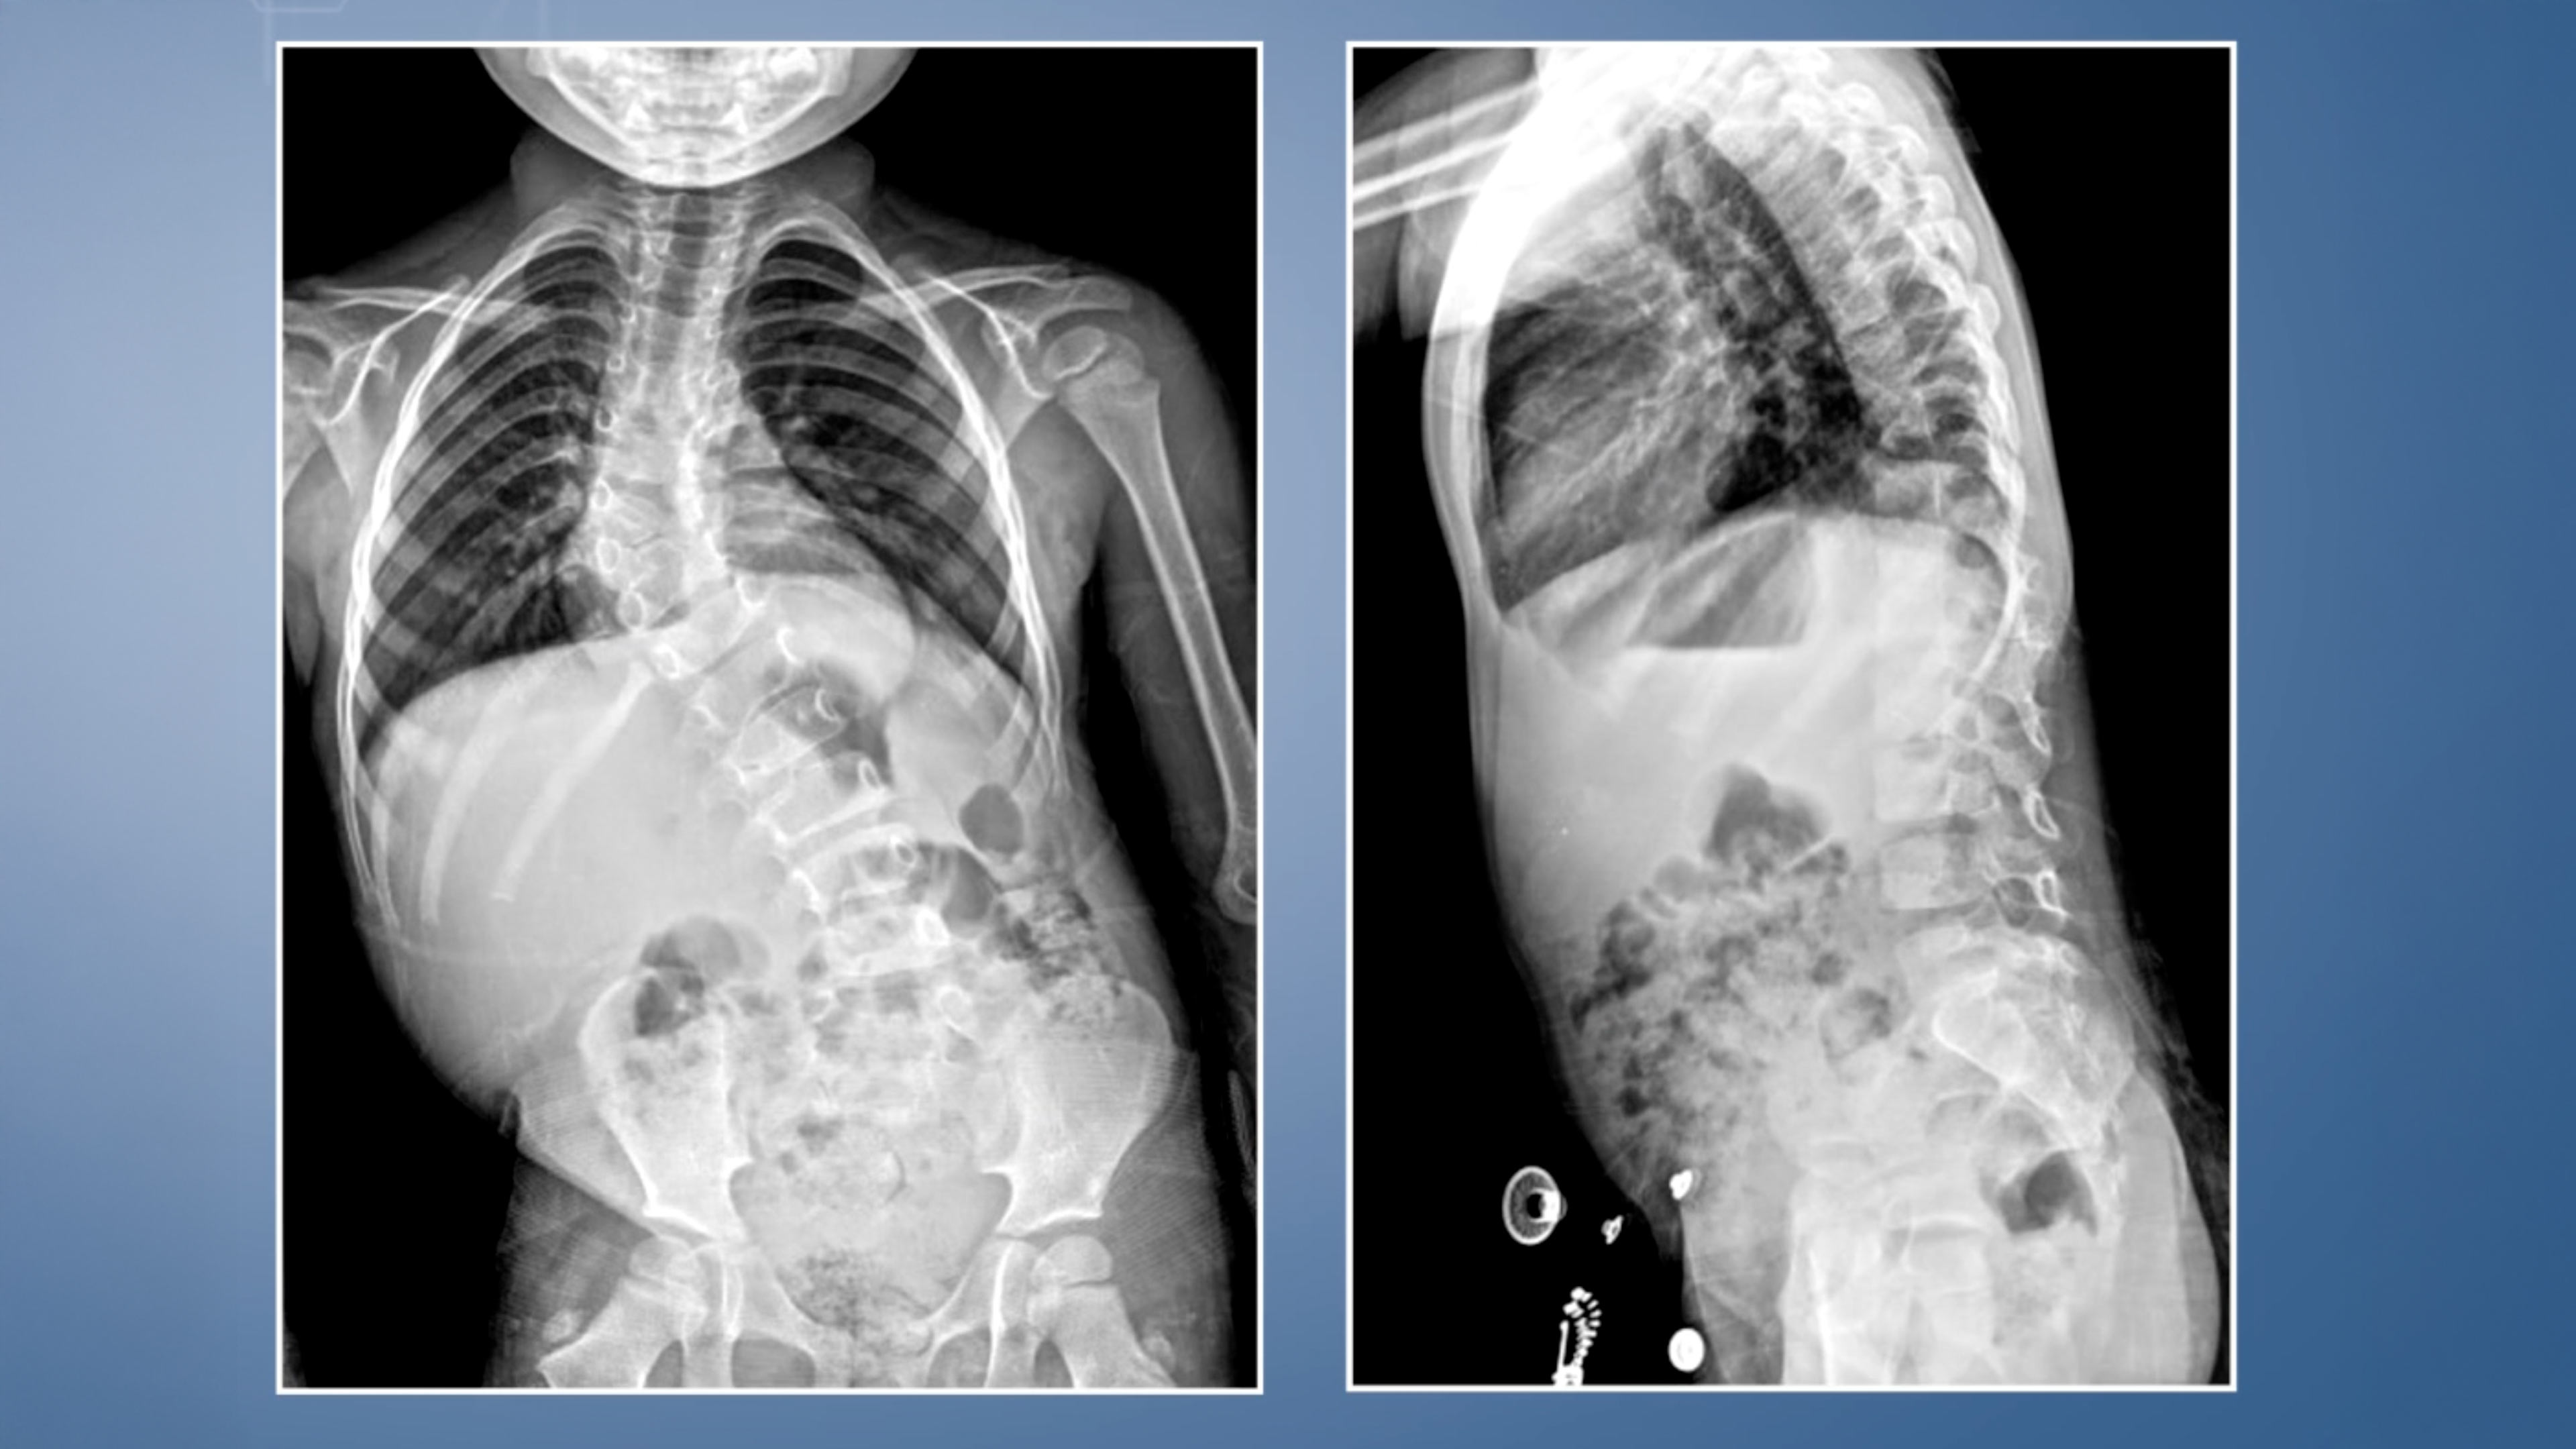

• Congenital Thoracolumbar Kyphoscoliosis

Congenital Thoracolumbar Kyphoscoliosis

Surgeons:

Antaranyan Ara MD

Wigmore Women's & Children's Hospital

Yerevan Armenia

Aebi Max MDl

Bern Switzerland

Project 24-013

We present another case of a congenital kyphoscoliosis in a 8-year-old girl, in whom we resected the posterior joints at the le...